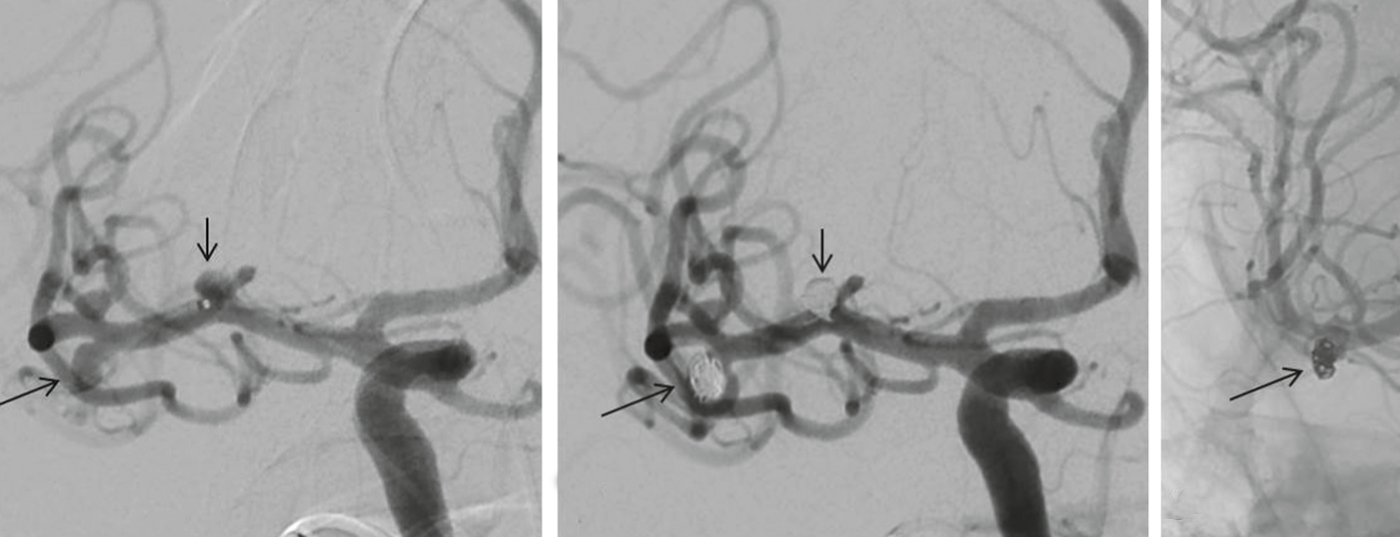

• Okklusionstherapie intrakranieller Aneurysmen

Endovaskuläre und neurochirurgische ­Möglichkeiten

Eine aneurysmatische Subarachnoidalblutung (aSAB) ist mit hoher Mortalität und Morbidität vergesellschaftet. Nach initialer Stabilisierung des Patienten muss durch neurochirurgische und/oder endovaskuläre Therapieformen die Blutungsquelle ausgeschaltet werden. Aneurysmen, die für beide Therapie­optionen in Frage kommen, sollten bevorzugt endovaskulär ­behandelt werden. Dennoch eignet sich nicht jedes Aneurysma für die endovaskuläre Therapie und die chirurgischen Möglichkeiten haben bis heute einen klaren Stellenwert. Aufgrund des minimal-invasiven Charakters und der fortschreitenden Weiterentwicklung der endovaskulären Methode ist dennoch mit ­einer Zunahme dieser Therapieform zu rechnen. Die vorliegen­de Arbeit soll die Möglichkeiten beider Therapieoptionen vorstellen.